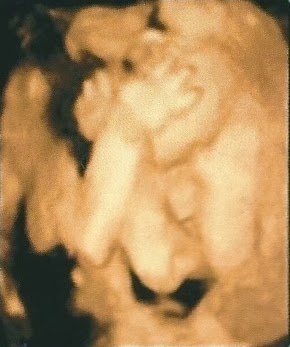

Incrível como está tudo formadinho com apenas 12 semanas, ficamos muito emocionadas em ver seu rostinho, dedinhos, boca, orelha ... tudo perfeito!

Tivemos a ideia de fazer o convite do chá de bebê com a foto do ultrassom (24 semanas). O médico riu muito no consultório, porque o tempo todo ele cobria o rosto com as mãos. Por um segundo o médico conseguiu pegar o rostinho dele, que serviu para o convite! Sempre fazendo graça!